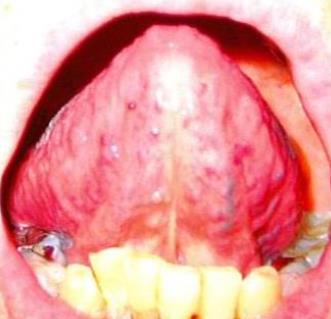

【2013年3月8日・漢方薬服用薬の舌表】

舌は浮腫んでいるのですが 細く小さい

血や気や津液の不足で栄養不足の舌です

白の厚い苔ややや黄色の苔 ぶつぶつ隆起

冷えや熱や火が体にあります